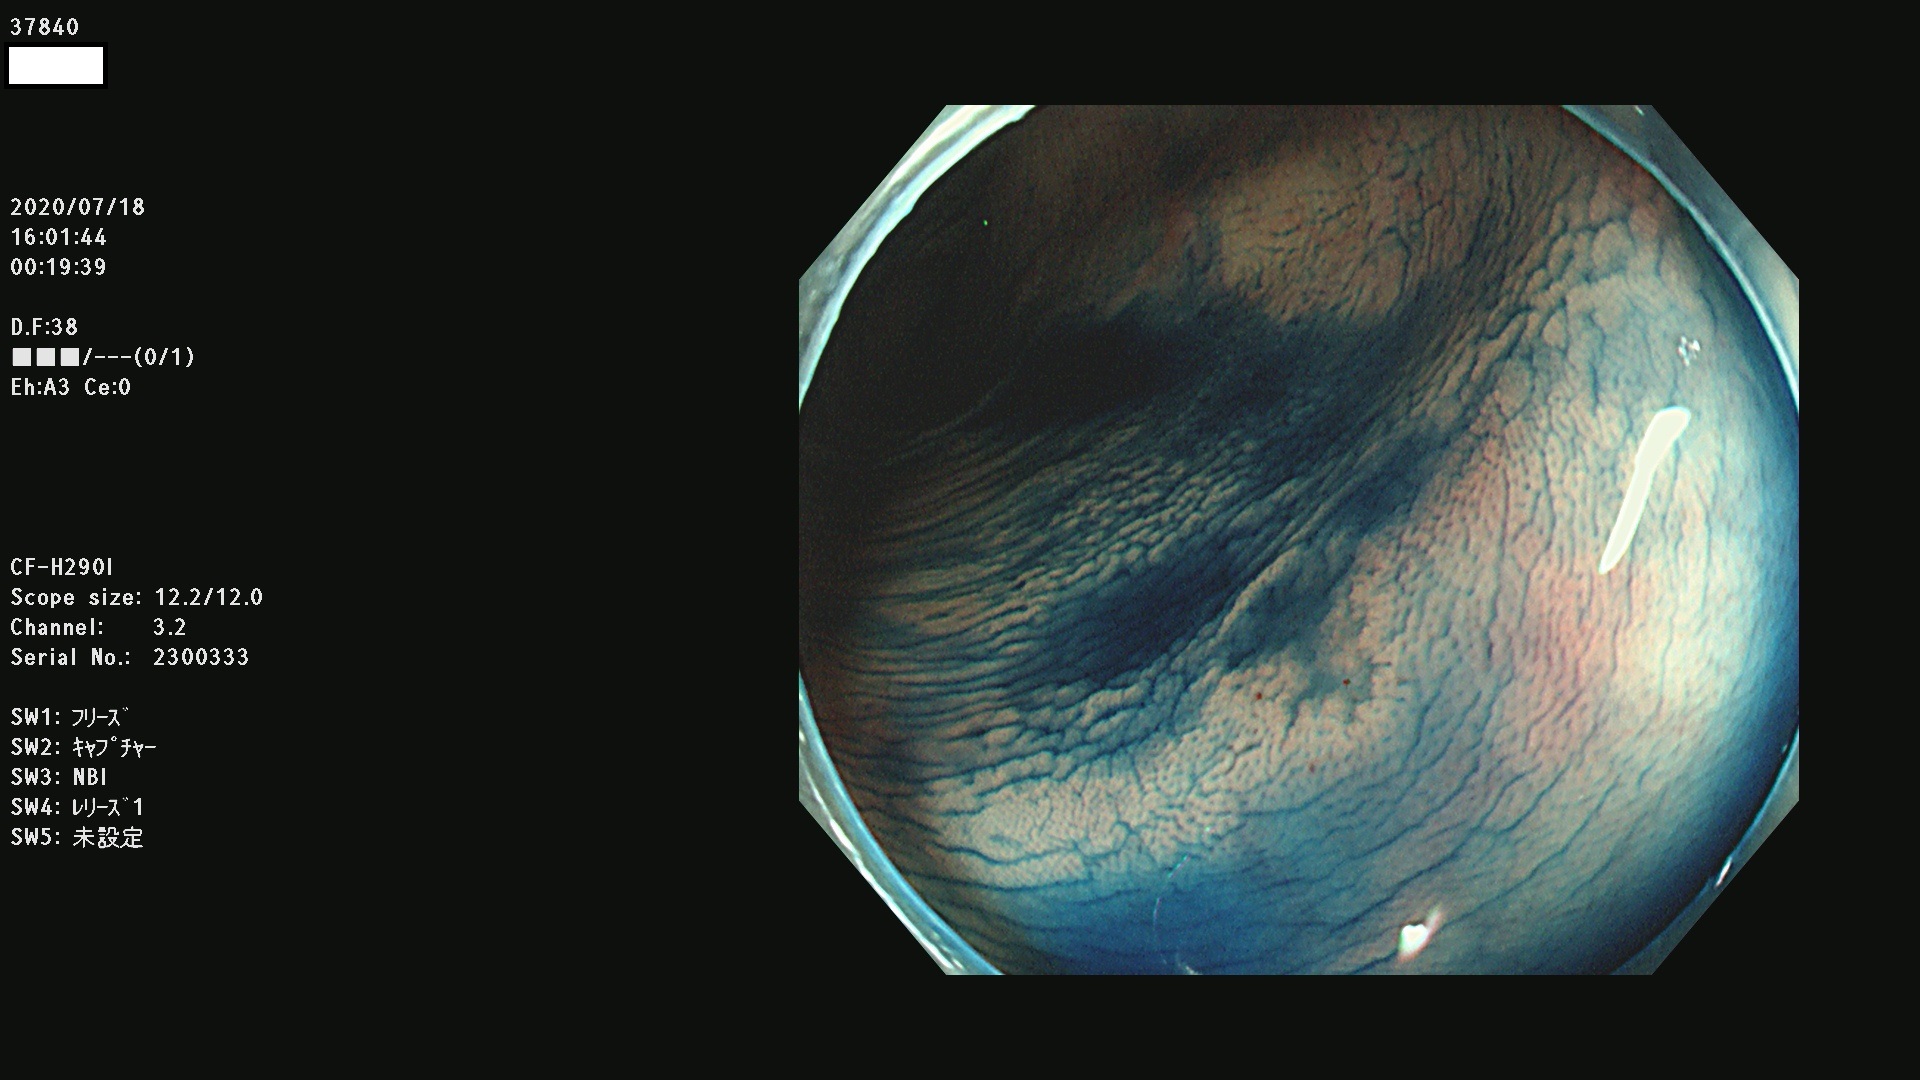

腺腫発見率 75 % (カルテ番号 37800〜37899の100名の方の検査結果で集計)大腸癌検診最新情報

以下のカルテ番号の方に腺腫(Adenoma,Group3〜5)が見つかりました(集計法)

37800(SSAPのみ) 37801 37802 37803 37804 37805 37806 37807 37808 37809(SSAPのみ) 37810 37811 37812 37813 37814 37815 37817 37818 37819 37820 37821 37822 37824 37825 37826 37827 37828 37829 37832 37833 37836 37837(SSAPのみ) 37839 37840 37842 37844 37845(SSAPのみ) 37847 37849 37850 37851 37852 37853(SSAPのみ) 37855 37856 37857 37860 37861 37862 37863 37864 37867 37868 37871 37874 37876 37877 37879 37880 37881 37882 37883 37886 37887 37888 37889 37890 37891 37892 37893 37894 37896 37897 37898 37899

発見困難で危険性の高い平坦型病変(上記100名より抽出) ![]()